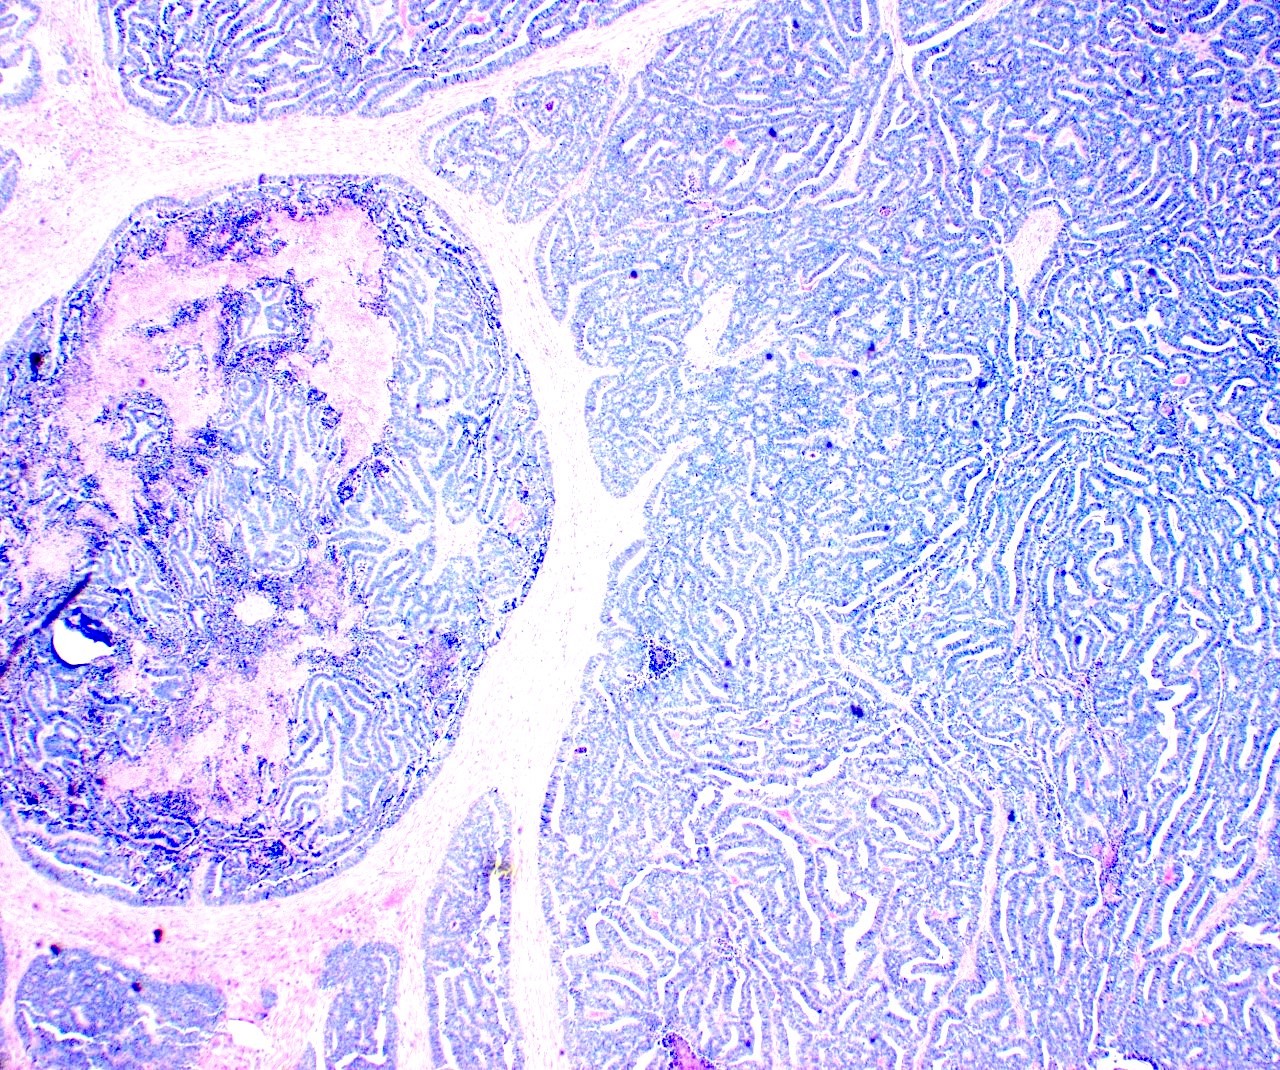

- Variety of histologic patterns that may be present within the same tumor

- Most frequently small tubules with ductal / glandular growth

- Papillary, solid growth, trabecular, retiform, sex cord-like, sieve-like, glomeruloid and spindle cell areas have all been described

- Luminal eosinophilic secretions are characteristic but not always identified

- Tumor cells can be flattened, cuboidal or columnar with mild to moderate cytological atypia

- Clear cell features can be seen but are less common

- High grade cytological atypia is usually not a predominant feature

- Nuclei show vesicular chromatin and nuclear grooves

- Sarcomatoid transformation has been seen in rare instances

- Squamous, ciliated or mucinous differentiation (metaplasia) are not present and there are no associated mesonephric remnants (J Clin Med 2021;10:698)

Microscopic (histologic) images

Contributed by Daniel Graham, M.D., Adele Wong, M.B., B.Ch., B.A.O. and Lucy Ma, M.D.